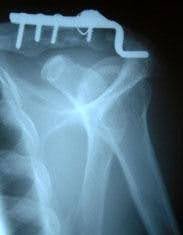

It is recommended that these injuries be treated early with surgical reduction using a special plate and/or wires with repair of the torn ligaments. Once stabilised, shoulder exercises can be started early to reduce shoulder stiffness.